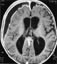

I dette nummeret Les mer om ... () sporsmal_grey_rgb Artikkel Transportfødsler Transportfødsler 133 kvinner fødte under transport til sykehus i Oppland i perioden 1989 – 97. Ett barn døde under fødselen. 71 % av kvinnene fikk hjelp av jordmor under fødselen, og en vaktordning for jordmødre anbefales. Fødsler utenfor fødeinstitusjon og kort tid etter ankomst Hydrocephalus Hydrocephalus En oppfølging av 128 barn som har fått shuntbehandling for hydrocephalus i årene 1985 – 88 viser at en femdel er døde. Tre firedeler av de overlevende gikk i vanlig skoleklasse, og halvparten av foreldrene oppgav at utviklingen hadde vært «meget bra» i forhold til hva de først trodde. Hydrocephalus hos barn Nevrokirurgisk shuntbehandling av barn med hydrocephalus Magnetisk resonanstomografi Magnetisk resonanstomografi MR-teknologi er blitt en viktig del av nevroradiologien, men også ved hjertesykdom kan MR være et supplement til andre diagnostiske metoder. Magnetisk resonanstomografi av hjertet Nevroradiologisk magnetisk resonanstomografi – indikasjoner og bruksområder Subluksasjon av radiushodet Subluksasjon av radiushodet Hos små barn er subluksasjon av radiushodet en vanlig skade etter drag og rykk i armen. Reponering gjøres ved supinasjon av underarmen. Subluksasjon av radiushodet – Fristilling, ikke frislipp – Fristilling, ikke frislipp Den nye helseministeren Tore Tønne er mer forbauset over likhetene enn over ulikhetene mellom bedrifter i offentlig og privat sektor. Trygg i helsetrøya Langtidsledige Langtidsledige Langtidsledige har tre ganger så høy risiko for depresjon og dobbelt så høy risiko for somatoforme sykdommer og angstsykdommer som normalbefolkningen. Har legene mer å tilby dem enn psykiatriske diagnoser? Arbeidsledighet og psykiske vansker Helse og livskvalitet blant langtidsledige Bekhterevs sykdom og HLA-B27 Bekhterevs sykdom og HLA-B27 Til tross for at HLA-B27 er sterkt assosiert med Bekhterevs sykdom, egner testen seg likevel ikke for å påvise sykdom. HLA-B27 ved Bekhterevs sykdom Kommentarer ( 0 ) Dette kommentarfeltet modereres, men kommentarer blir ikke redaksjonelt behandlet ut over å sikre at de følger retningslinjer for vårt kommentarfelt. Denne artikkelen ble publisert for mer enn 12 måneder siden, og vi har derfor stengt for nye kommentarer. Publisert: 30. april 2000 Utgave 11, 30. april 2000 Tidsskr Nor Lægeforen 30. april 2000 Publisert: 30. april 2000 Utgave 11, 30. april 2000 Tidsskr Nor Lægeforen 2000 PDF Får du ikke vist PDF-filen eller vil lagre filen, kan du høyreklikke på PDF-ikonet. Velg «Lagre mål/fil som..» og hent så opp PDF-filen i for eksempel Acrobat Reader. Skriv ut Anbefalte artikler